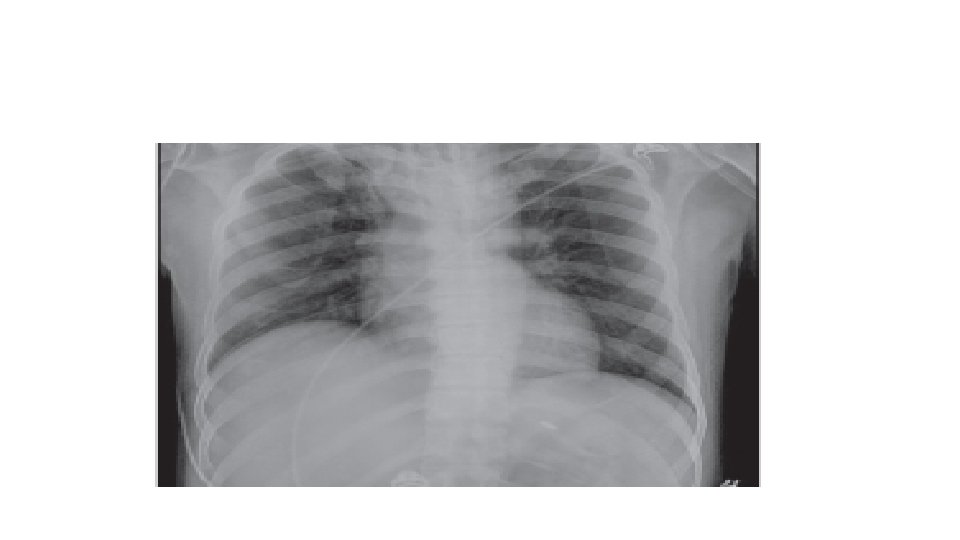

TACO SIGNOS Y SINTOMAS: Taquicardia, disnea, taquicardia, aumento de presion arterial sistólica y diastólica, pulsos saltones, estertores, saturación baja Radiografia : Cardiomegalia e infiltrados bilaterales , Lineas de Kerley , redistribución vascular hacia los apices, derrame pulmonar bilateral. PVC, PAP en cuña elevadas, Saturación bajas. Peptido natruretico cerebral Aumentado. 9

Criterios de reporte para TACO Deben de tener compromiso respiratorio agudo o que empeora durante o hasta 12 horas después de la transfusión y deben de mostrar dos o más de los siguientes criterios: Ø Evidencia de edema pulmonar agudo o que empeora con base en: • Examen físico (crepitaciones en la auscultación pulmonar, ortopnea y tos, cianosis y disminución de los valores de saturación de oxígeno) y/o • Imágenes radiográficas de tórax (nuevos y empeoramientos de derrames pleurales, edema alveolar y agrandamiento de la silueta cardiaca) Ø Evidencia de cambios en el sistema cardiovascular no explicados por la condición médica subyacente del paciente) incluido el desarrollo de la taquicardia, hipertensión, distensión venosa yugular y edema periférico. 12

CRITERIOS En pacientes sin evidencia de lesión pulmonar aguda (ALI) antes de la transfusión, se diagnostica TRALI si hay un nuevo ALI y deben de cumplirse los cinco criterios: Ø Inicio agudo Ø Hipoxemia con: • Pa. O 2 ( presión parcial de oxígeno)/Fi. O 2 (fracción inspirada de oxígeno) menor o igual a 300 mm. Hg, Cociente que mide indirectamente la lesión pulmonar o • La saturación de Oxígeno es de <90% • Otras evidencias clínicas Ø Infiltrados bilaterales en la Rx de tórax Ø No hay evidencia de hipertensión auricular izquierda (sobrecarga circulatoria) Criterios revisados en 2017 Ø No hay relación temporal con un factor de riesgo para lesión pulmonar durante o dentro de las 6 horas posteriores al término de la transfusión 23